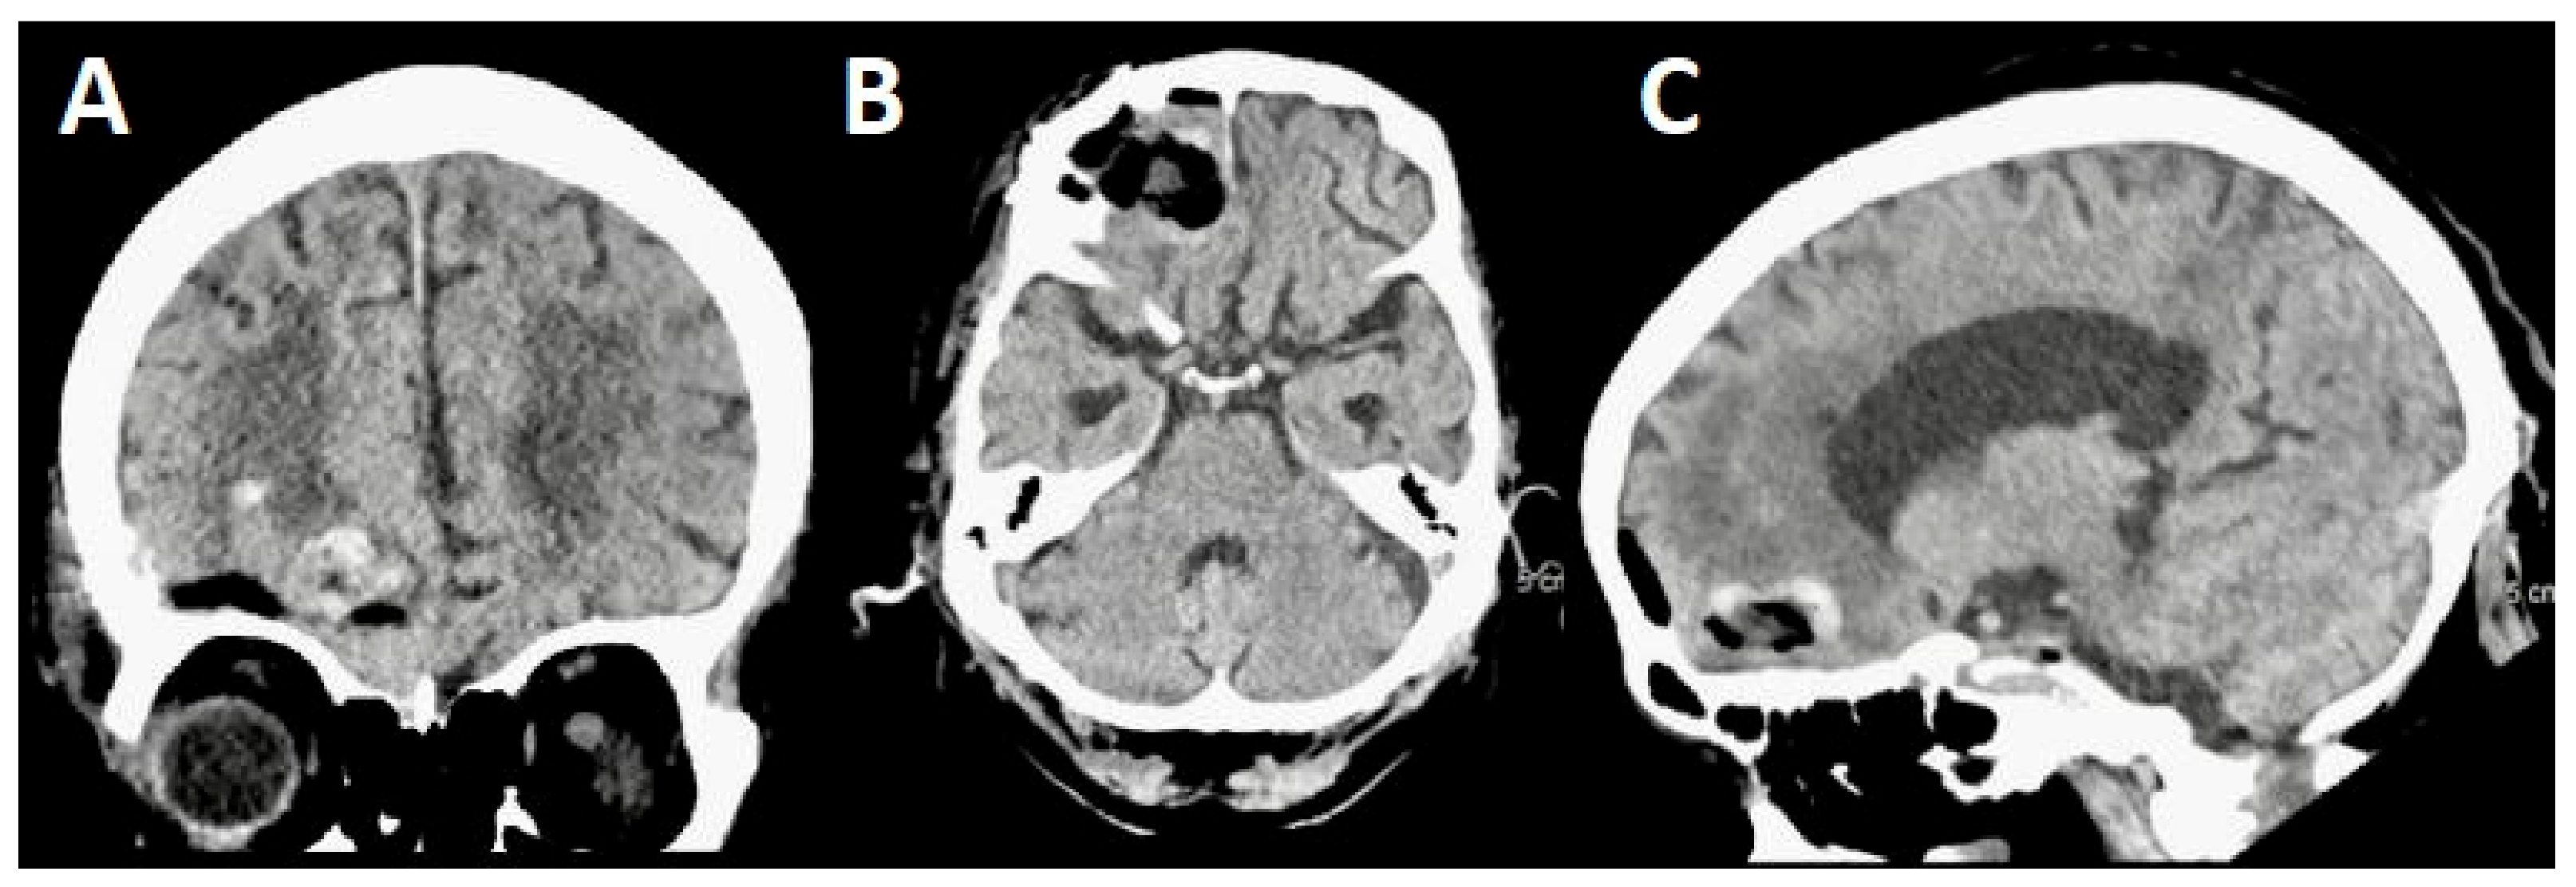

3.2. Case 2

3.2.1. Demography, Presentation, and Evaluation

3.2.2. Intervention

3.2.3. Postoperative Period